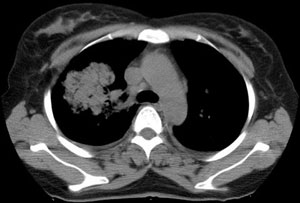

女性,30岁。

病史为胸痛20多天,无畏寒发热,无消瘦,无咳嗽咳痰。总之症状很逍遥。

临床以胸痛待查收住入院。

双肺野可见散在大小不等结节及肿块影,内密度不均匀,边缘部分清,部分欠清,纵隔未见明显肿大淋巴结.右侧胸腔少理积液.结合临床,考虑韦格肉芽肿可能吧,巨淋巴增生,结节病,特殊感染都要考虑.转移瘤临床不象.

本病例特点如下:

1.青年女性,以胸痛20多天就诊,无呼吸道及感染临床症状体征,无原发肿瘤病史;

2.肺ct表现为两肺多发大小不等结节影,大结节位于肺尖部,小结节多位于肺外带胸膜下,大结节内可见支气管充气征,周围可见月晕征(指在结节状或肉芽肿样病灶周围呈环形磨玻璃影),右肺门及腔静脉后可见小淋巴结,右侧胸腔内少量液体。

两肺散在分布大小不等的肿块及结节影,边缘毛糙,有分叶、毛刺,病灶密度不均匀,可见支气管充气相与空泡征。病变大多位于胸膜下,可见胸膜凹陷及胸腔积液。气管腔静脉间可见小结节影。

病人临床仅为胸痛,暂不考虑感染性病变。

考虑多发结节型细支气管肺泡癌。